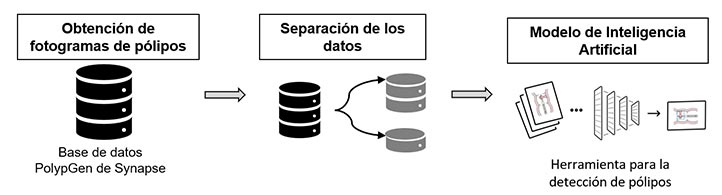

Los modelos de IA son entrenados para la detección con imágenes de casos reales para su comparación

“Nosotros alimentamos la IA con una base de datos de imágenes vasta y la entrenamos, se dice que es un aprendizaje supervisado porque primero el médico va calificando como lesión de bajo grado, de alto grado o una infección, y a partir de ese etiquetado aprende a relacionar nuevos casos, se crea un modelo matemático y a partir de esto desarrollamos sistemas de apoyo a la toma de decisiones del experto, nunca consideramos sustituirlo, es más bien darle herramientas para que tenga una segunda opinión o facilitar que haya un experto artificial en lugares donde el humano no pueda tener un fácil acceso”, agregó el entrevistado.

En la actualidad han comenzado un nuevo proyecto, enfocado en la detección de pólipos colorrectales, dado que el cáncer colorrectal es la segunda causa de muerte a nivel mundial entre hombres.

El investigador puntualizó que la idea es detectar a tiempo los diversos tipos de pólipos y determinar si son malignos o benignos, aplicando las técnicas de visión por computadora, específicamente en el área de imagenología médica.